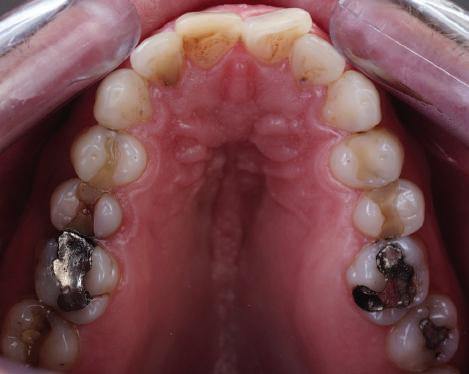

Пациентът постъпи в моята клини ка с наличие на темпоромандибуларен дисфункционален болков синдром, едно странно изместен диск с редукция в дяс ната става, клас II, подклас 2, тесни гор на и долна челюст със струпване, дъл бок овърбайт

орални снимки и снимки на позата, пал пация на мускулите, брукс-чекър, оклу зограми, кондилография, рентгеногра фии, СВСТ и ядрено-магнитен резонанс на темпоромандибуларните стави). Преди началото на ортодонтското лечение всички стари възстановява ния бяха свалени и бяха заменени с дъл госрочни временни от хибридна керами ка. На девитализираните зъби бе прове дено ендодонтско релечение. Индивиду ализиран оклузален сплинт бе направен с цел да се постигне контролирано репо зициониране на долната челюст, като носенето му продължи три месеца до възстановяване на правилната позиция на ставния диск и затихване на орофаци алната болка и дискомфорт в ставата. Брекетите в горната челюст бяха за лепени, за да започне подреждането и нивелирането на зъбите, докато паци ентът все още носеше сплинта. След края на терапията със сплинта бе на правена кондилография, за да се потвър ди триизмерната позиция на долната челюст. След залепване на брекетите в долна

и гингивална усмивка. Започнахме лечението с пълна диагно стика (анамнеза, интраорални, екстра